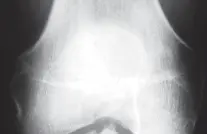

التصوير الطبي ضروري لتأكيد التشخيص وتحديد مدى تلف المفصل:

-

الأشعة السينية العادية (Plain Radiographs):

- المنظر الأمامي الخلفي (AP): يُظهر الركبة من الأمام.

- المنظر الجانبي (Lateral): يُظهر الركبة من الجانب.

- المنظر الخلفي الأمامي المثني (PA Flexed): يسمح بتقييم أفضل للجزء الخلفي من الركبة وقد يكشف عن تغيرات أكبر في الحجرة الخلفية الوحشية.

- منظر شروق الشمس (Sunrise/Patellofemoral): لتقييم المفصل الرضفي الفخذي.

- الأشعة السينية الطويلة للطرف السفلي بالكامل (Full-length standing radiographs): من الورك إلى الكاحل، وهي مفيدة جدًا، خاصة إذا تم استخدام تقنيات الملاحة الحاسوبية. تُظهر هذه الأشعة المحاذاة الكلية للطرف السفلي.